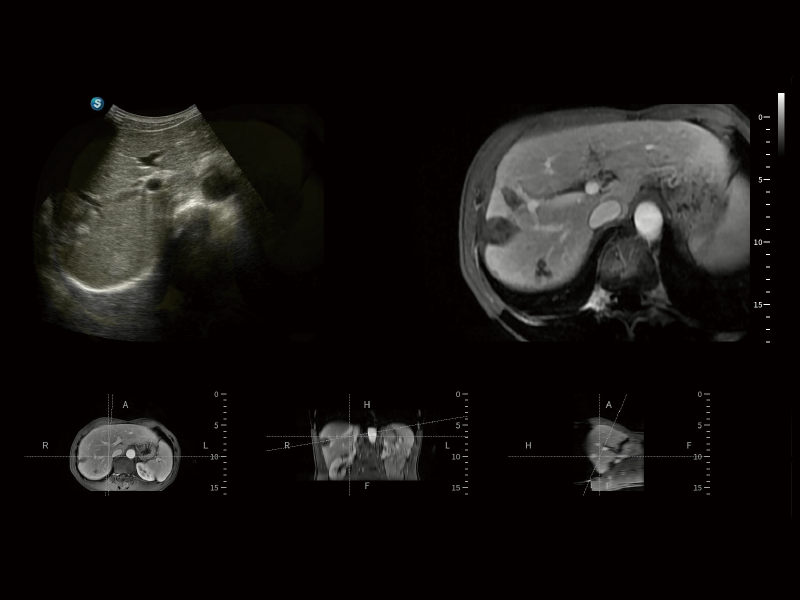

作为开立医疗全新打造的超高端旗舰超声产品,从探头抬起唤醒开启扫查到多维探头发射接收,通过先进的场成像发射、自适应聚合重建等技术,基于RF Data原始射频数据在图像生成、高端功能等方面实现突破,提供多科室综合临床解决方案。

S80 提供多样化超声成像技术,可满足不同科室的需求,在助力扫查诊断和介入治疗中发挥着重要作用。